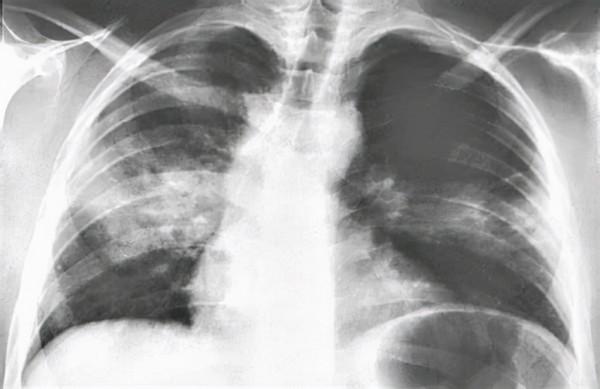

有的患者開始出現咳嗽、咳痰、呼吸困難、口唇發紺、煩躁,入院後很快發展為重症肺炎。

人感染鸚鵡熱衣原體之後的臨床表現是多樣的,有一些人甚至完全沒有症狀,或者症狀比較輕微。也有一些人急性發病,表現為非典型的肺炎。

一旦得了鸚鵡熱,如果沒有經過有效的治療,死亡率可達10%左右,主要是因為部分患者會發展成為重症肺炎。

隨後大多數患者可有呼吸道症狀,約80%的患者會出現咳嗽、呼吸困難、胸痛和咳血,但也有一些人沒有呼吸道症狀。